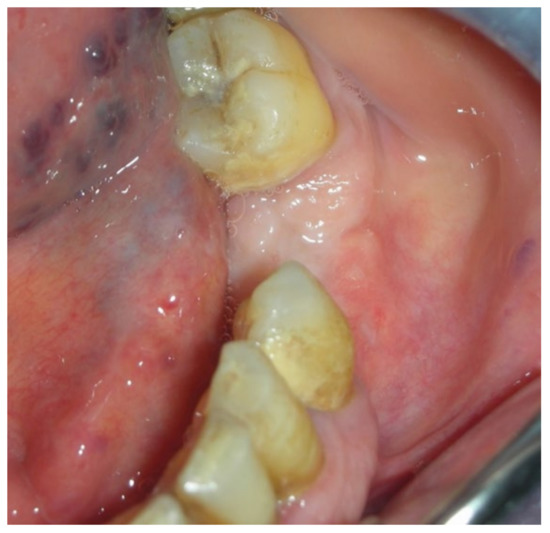

3.1. Clinical Case 1

3.2. Clinical Case 2

3.3. Clinical Case 3

3.4. Clinical Case 4

3.5. Clinical Case 5

3.6. Clinical Case 6